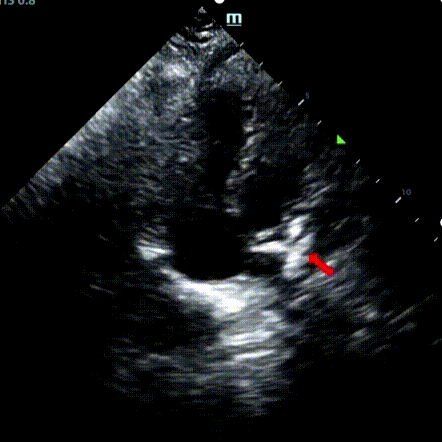

Secundum asd (7.5-7.9mm) ile 9 yaşındaki bir erkek, memosorb BDASD-I 12mm occluder ve 12f dağıtım sistemi kullanılarak tedavi edildi. Komplikasyonlar veya komorbiditeler ön prosedür olarak belirtilmedi.

Serial echocardiographic follow-ups showed stable device position and favorable cardiac remodeling. Gradual degradation confirmed the occluder's long-term safety and efficacy.